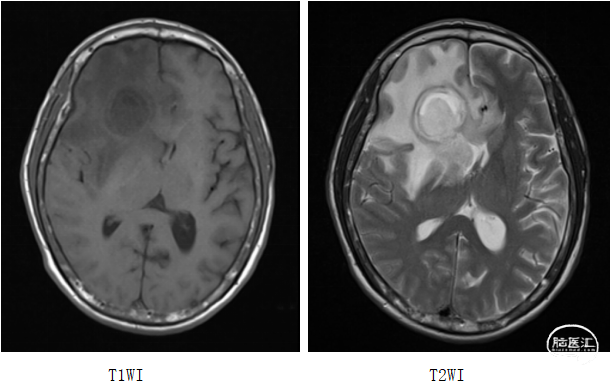

作者:刁艺

基本情况:患者钟xx,女,58岁。

主 诉:间歇性头痛半月余。

查 体:神志清楚。瞳孔正常。无嗅觉减退。余无明显阳性体征。